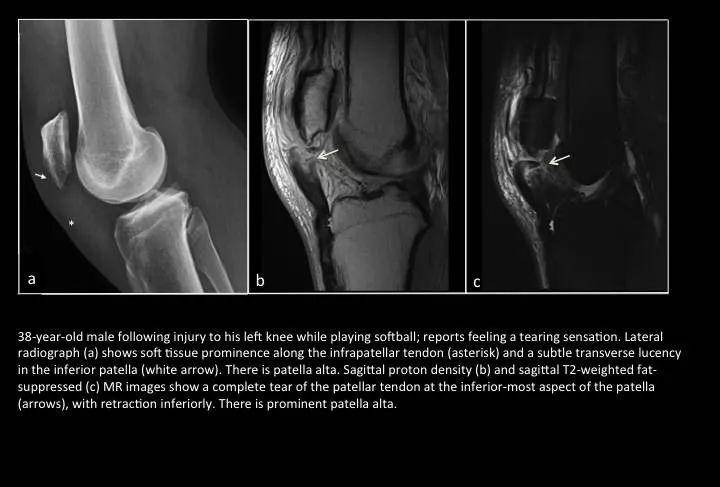

Fig. 20: Patellar tendon rupture

图20:髌韧带断裂